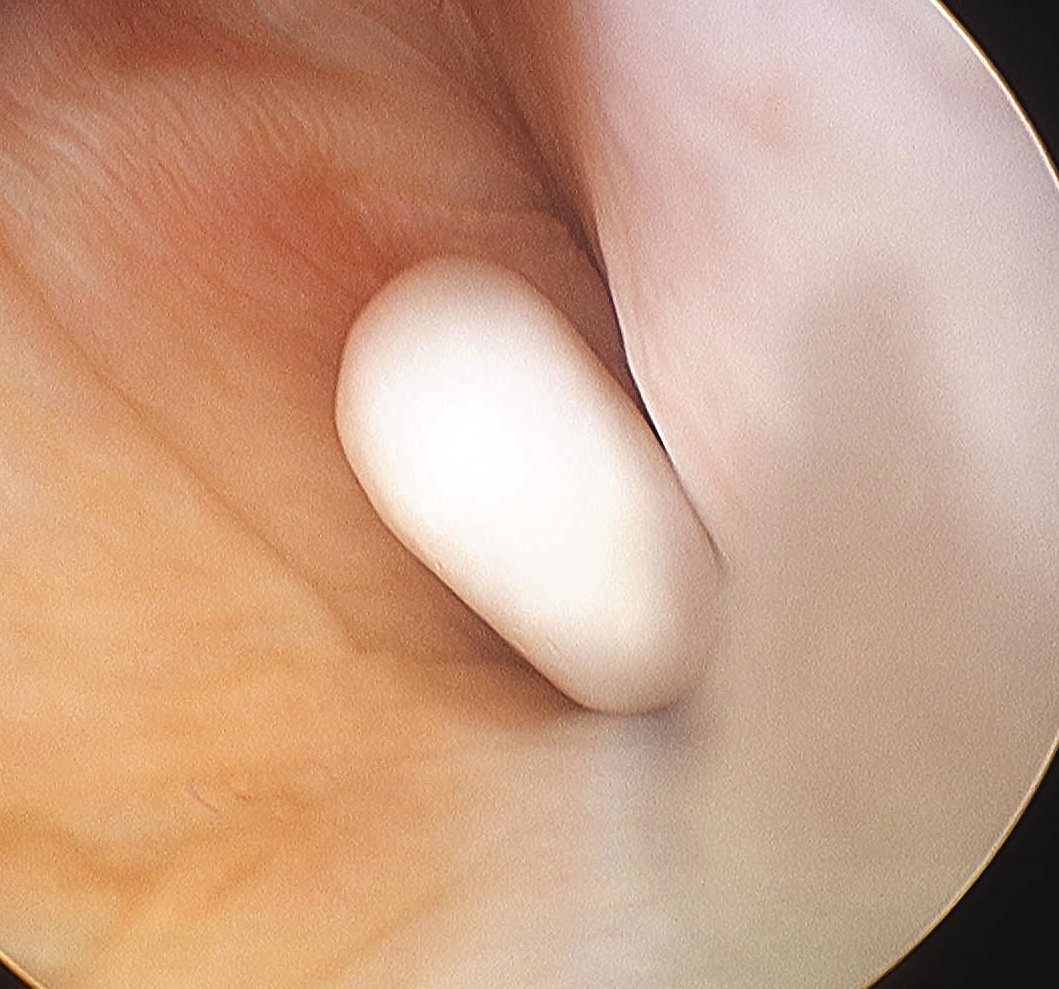

2 x Osteochondral Fragments in Notch

Osteochondral Fragment in PFJ

Loose body in posterolateral compartment